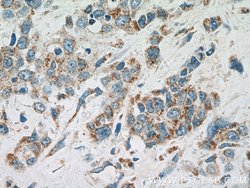

| Western Blot, Immunohistochemistry (Paraffin) | |